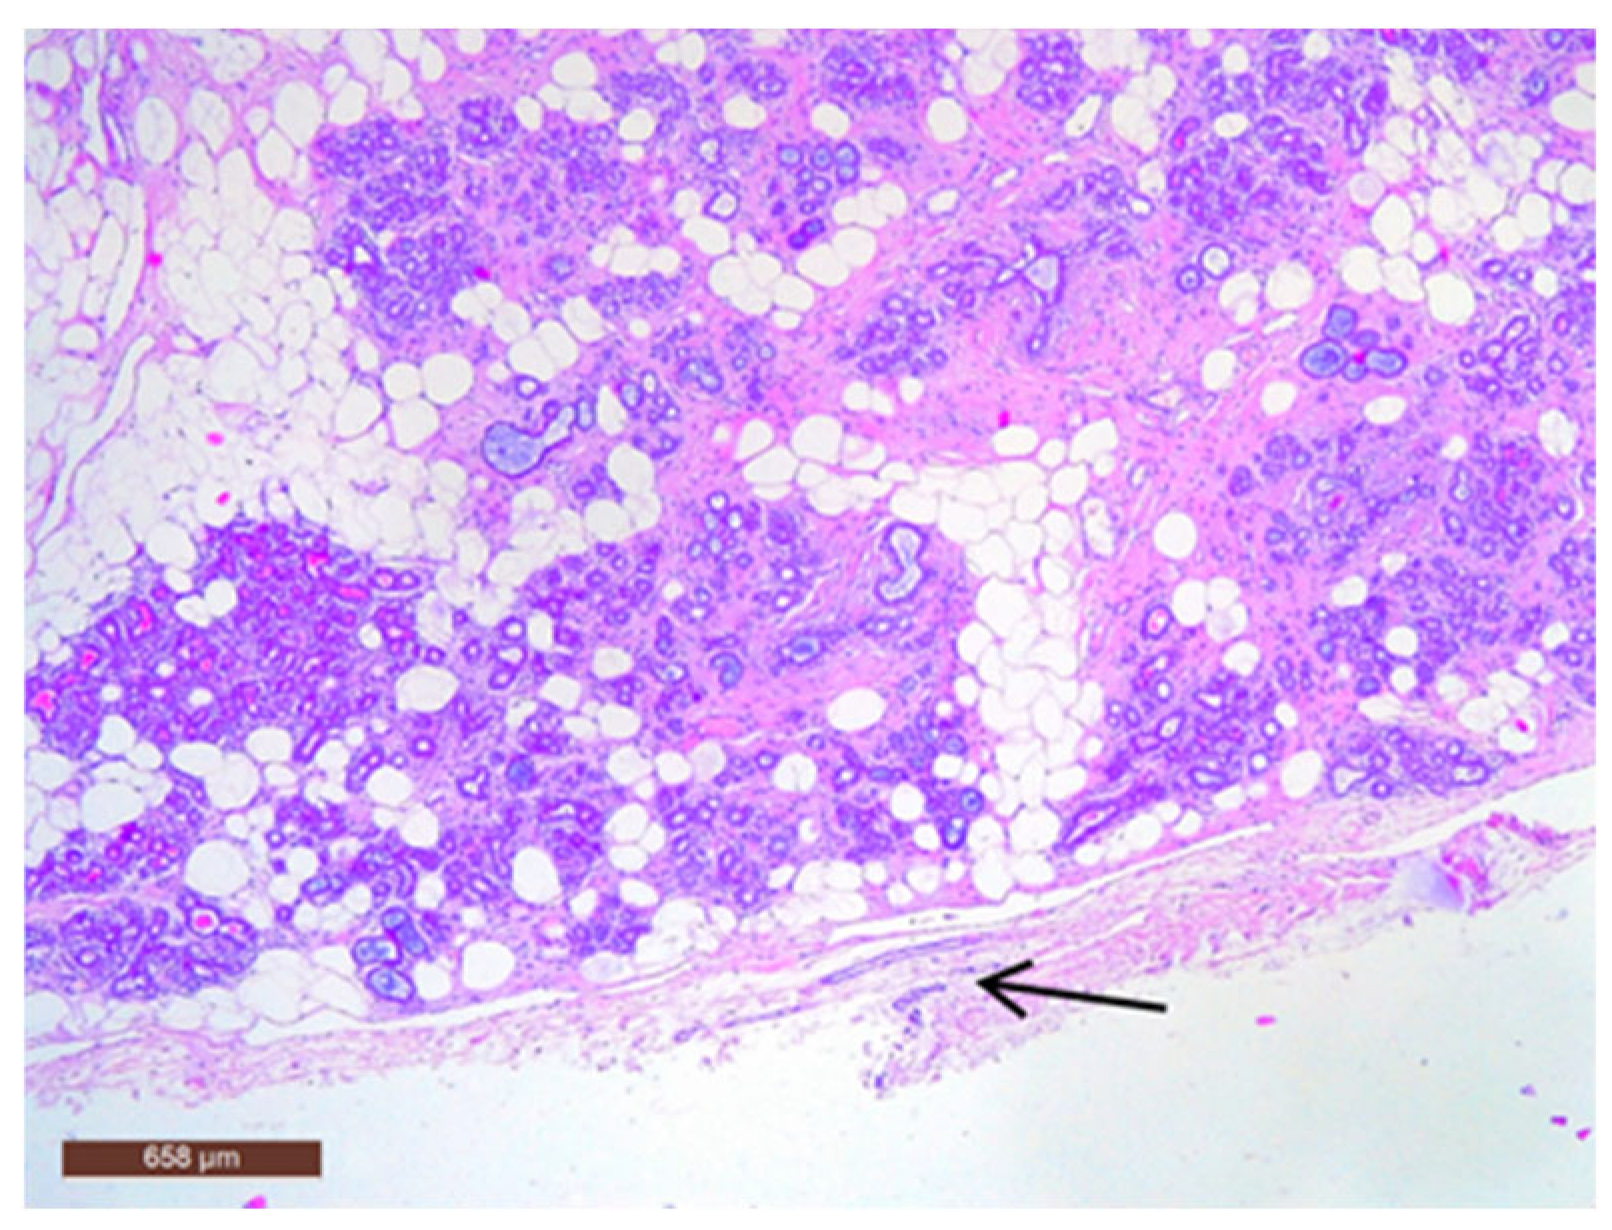

On microscopic examination, a hamartoma may exhibit three predominant components: glandular, fibrous and adipose (Figure 7). Epithelial components such as ducts and lobules are generally normal, featuring a single layer of epithelium overlying the myoepithelial cells. The fibrous component was composed of connective tissue stroma with a delicate connective tissue capsule (Figure 8). Additionally, the ducts within the hamartoma may display apocrine metaplasia (Figure 9).

Figure 8. Hamartoma with fine connective tissue capsule (arrow) (HE ×40).